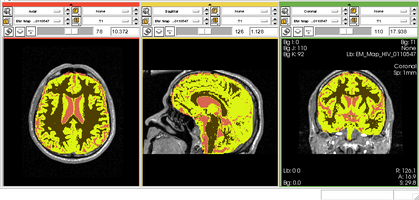

Physiological Brain Activity Longitudinal Study

- Collaborator: Laura Horky PI (Brigham and Women's Hospital(BWH)), Jon Hainer (BWH), Wendy Plesniak (BWH), Alexander Zaitsev (BWH), Ron Kikinis (BWH) and BWH Division of Nuclear Medicine

- Short description: Evaluate glycolitical brain activity in CSF and White Matter for the patients undergoing chemical therapy courses.

- Image specification: 1.5 Tesla ,Scanner: SIGNA EXCITE / GE MEDICAL SYSTEMS, T1, Axial Scans, TR/TI/TE=500/0/21 ms, pixel_xsize = 0.781251, pixel_ysize = 0.781244, fov = 0.000000, aspect = 7.679990, thick = 5.000000, space = 1.000000

- Used Task: MRI Human Brain Hemisphere